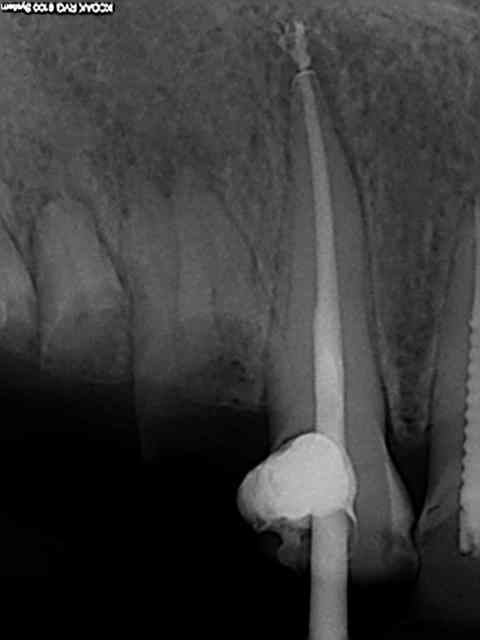

Comme celle là par exemple ? 20 ans et presque toutes ses dents )))) Mieux vaut avoir les radios initiales par les temps qui courent !

Je me demande quand meme si j'aurais pas du à cet age faire des coiffages directs avec biodentine. On va encore me reprocher de dégainer le r40 trop facilement. Tout frais de cet aprem.